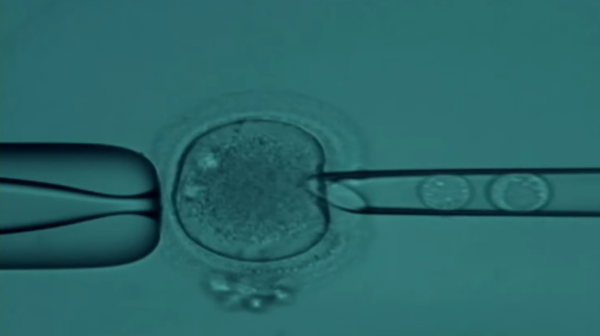

На программу бесплатного ЭКО в Абхазии выделят дополнительно 20 млн рублей